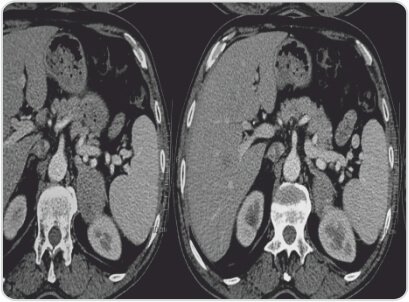

CT report shows evidence of well defined homogenous dense soft tissue lesion with few central hypodensities involving body and medial limb of left adrenal gland of 62x49x55mm, abutting lower pole of spleen, greater curvature of stomach and upper pole of left kidney.

Left adrenal mass with solid and necrotic areas – Left Adrenal Cortical Carcinoma.

Right kidney, right adrenal, liver, spleen, pancreas and gall bladder normal.

Axial and Coronal ct scan image showing left adrenal tumour